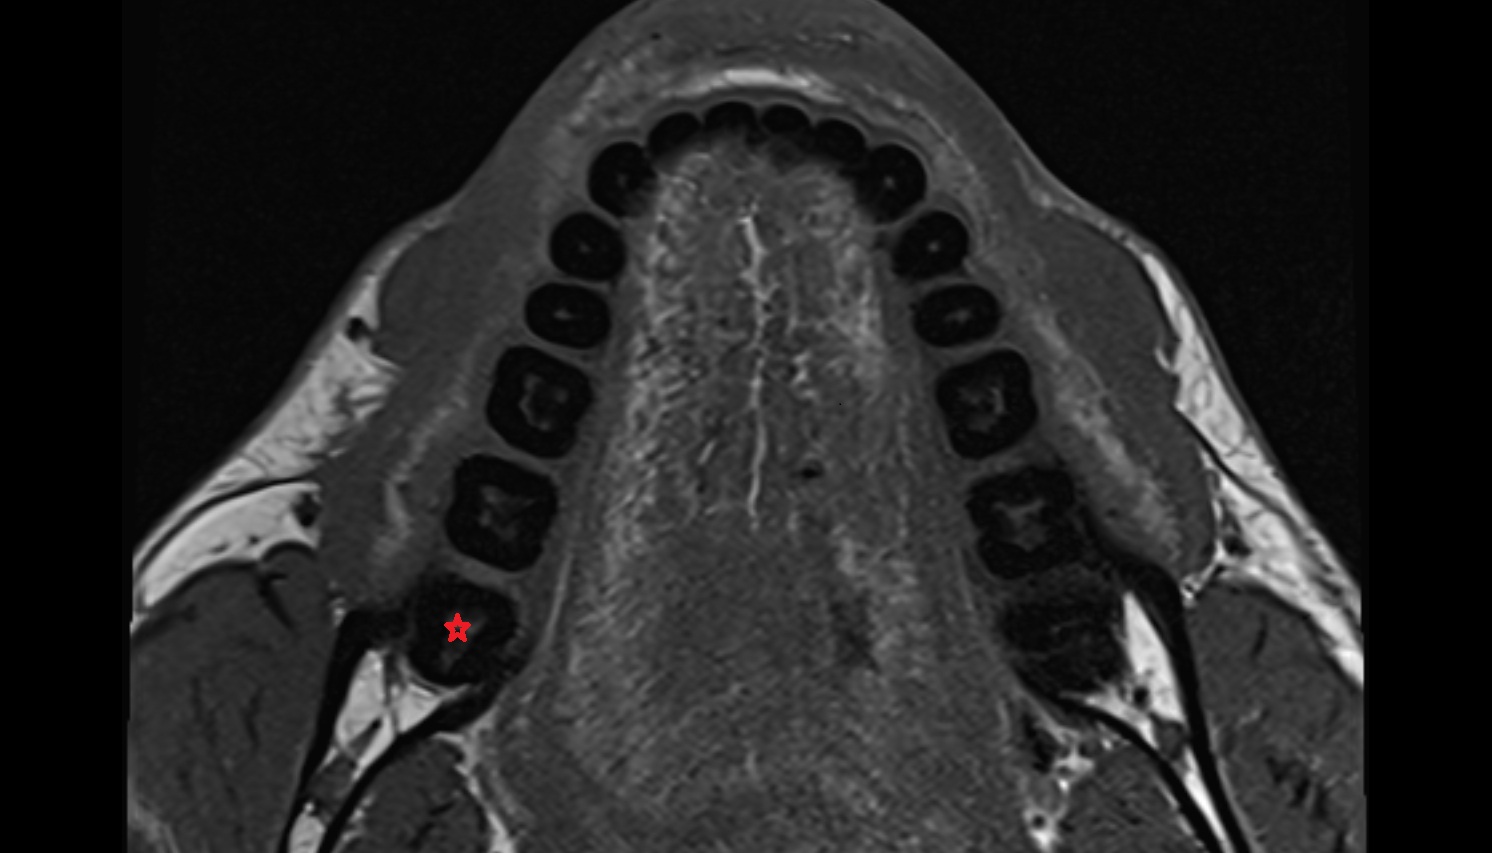

- Mandibular canal

- inferior alveolar artery

- Inferior alveolar nerve

- Mental nerve

- Inferior alveolar foramen (mandibular foramen)

- Mandibular foramen

- Root of lower molar tooth

- Lower molar apical foramen

- Upper premolar apical foramen

- Root of upper molar tooth

- Root canal of upper molar tooth

- Dental pulp of upper molar tooth

- Dental pulp of upper premolar tooth

- Enamel of lower molar tooth

- Mandibular nerve

- Dental pulp of lower molar tooth

- Root canal of lower premolar tooth

- Lower premolar apical foramen

- Dental branches of inferior alveolar artery, vein, & nerve

- Alveolar process of maxilla

- Superior dental plexus